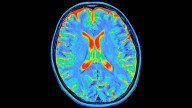

Can tattoos protect your skin from the sun's harmful rays, or do they make things worse? A new study I conducted with colleagues suggests there may be cause for concern.

We found that people with tattoos had a 29% higher risk of developing melanoma, a serious form of skin cancer often linked to ultraviolet (UV) exposure.

However, tattoos did not appear to increase the risk of squamous cell carcinoma, another type of skin cancer related to UV damage. Although both cancers share a common cause, they arise from different cell types and differ in severity, with melanoma being far more dangerous.